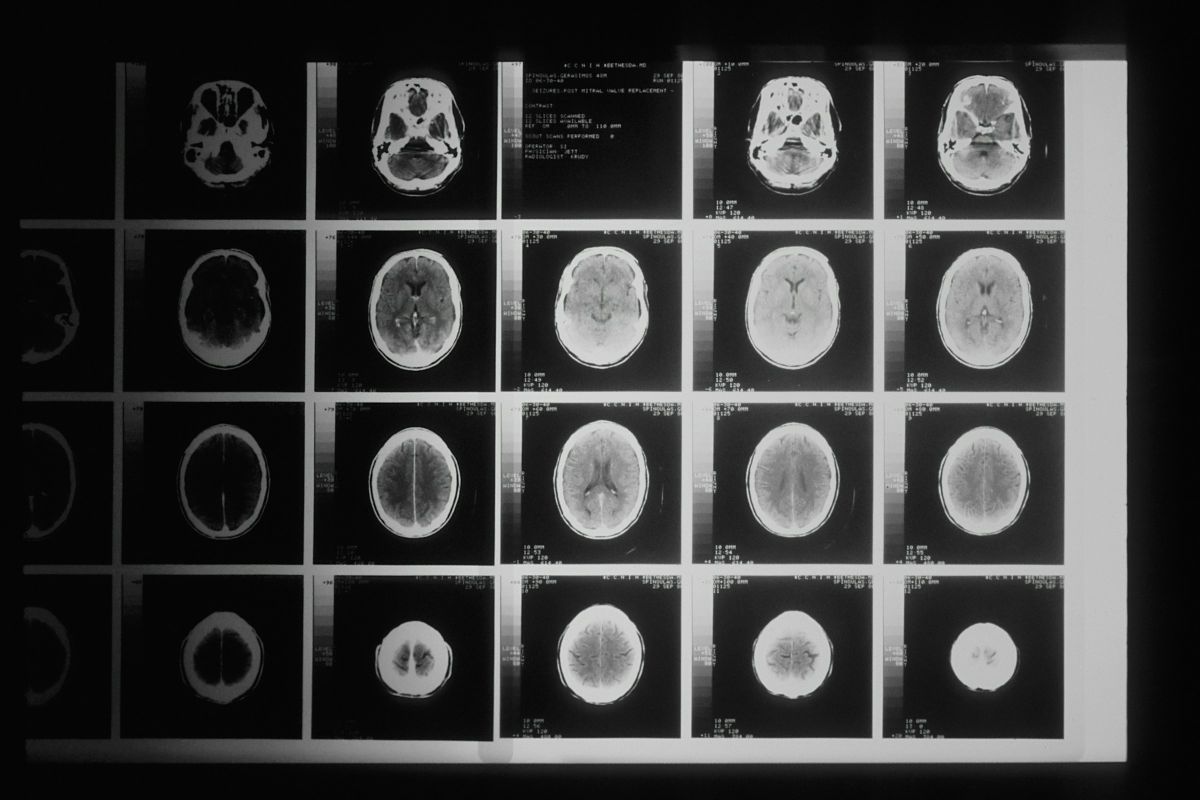

A fiatal több agyműtéten esett át, de már nem lehetett rajta segíteni.

December 17-én újabb műtéten esett át, amely során a daganat körülbelül 70%-át tudták eltávolítani. A beavatkozást követően James fertőzést kapott, ami jelentősen lassította a felépülését az orvosok várakozásaihoz képest.

Az angol fiatal egy negyedik stádiumú agydaganatban szenvedett, ezért később két további műtéten esett át. Sajnos a fiatal rohamot kapott, és mesterséges kómába helyezték. Öt napnyi életben tartó készülék használata után James felébredt.

Az orvosok ezután tudatták a tragikus hírt, a daganat teljes egészében visszanőtt onnan, ahol a 70%-át eltávolították. Három és fél-négy hét leforgása alatt a daganat teljesen visszanőtt, és úgy nézett ki, mintha az agy más részeire is átterjedt volna. James állapota gyorsan romlott, és hirtelen azt mondták nekik, hogy kevesebb mint 24 órája van hátra. James kilenc órával később meghalt, családja körében - írja a Mirror.